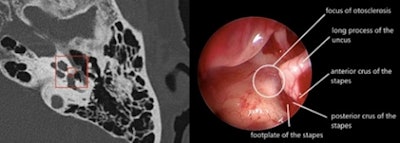

Regarding imaging, deep learning already allows clinical applications ranging from the automatic segmentation of anatomical structures, recognition of small pathologies such as otosclerosis, through to medical education, and even surgical planning with, in particular, facial nerve tracking. For otosclerosis, real performance results are at least equivalent to expert radiologists, even at stages I and II, also allowing differential diagnoses such as stapedial malformation or chronic otitis.

In a study using the algorithm developed using Cleverdoc tools and led by Oto-Med, the results of external validations of 124 cases studied on multibrand CTs, with otosclerosis confirmed surgically (Figure 2), were 96.6%, 95.3%, 95%, and 97% respectively for sensitivity, specificity, positive predictive value (PPV), and negative predictive value (NPV). The other tools developed relate to malformative and cholesteatoma pathologies and vestibular MRI. The future also lies in the integration of other biomarkers, whether clinical, biological, electrophysiological, anatomopathological, or genomic, to improve patient care.